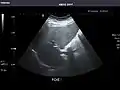

Left kidney